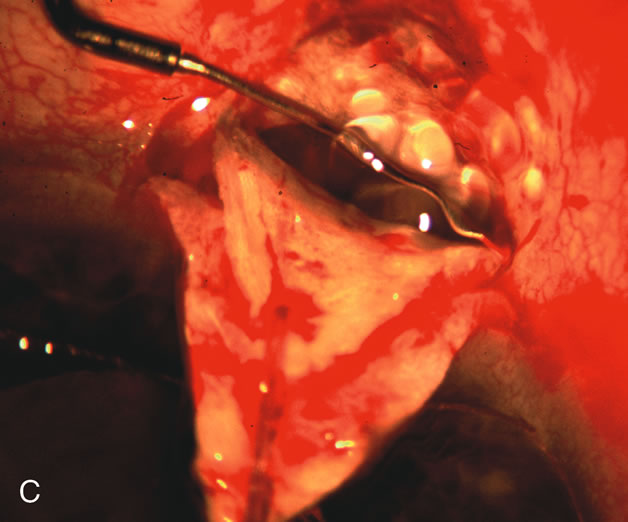

During preoperative slit-lamp biomicroscopy, the surgeon evaluates the condition of the conjunctiva and decides on a fornix-based or a limbus-based conjunctival approach.174–177 There are definite advantages and disadvantages of each approach (Table 3). With proper wound construction, there appears to be very little difference in long-term IOP control between the two incisional groups. However, the long-term bleb appearance varies considerably between the two incisional groups,178 with a limbus-based conjunctival flap more likely to develop a cystic bleb especially if an antimetabolite is used179 (Fig. 8).

Fig. 8. Bleb appearance after limbus-based versus fornix-based conjunctival flaps. Even though the IOP is thought to be equivalent between limbus and fornix-based conjunctival flaps, the final bleb appearance varies considerably. A. During a limbus-based approach, an incision through conjunctiva 10 mm posterior to limbus will sever through multiple arterial vessels, increasing the likelihood of an avascular bleb. B. The tissues are dissected down to the sclera further cutting feeder vessels from Tenon's capsule. C. The wound is closed inciting a cascade of wound healing events that may ultimately lead to scarring producing a barrier to aqueous flow. D. This leads to walling off of a bleb that has lost some of its overlying vascularity (pale cystic avascular bleb). E. During a fornix-based conjunctival approach, the incision is made at the limbus and tissues undermined. F. The incision is closed at the limbus; no conjunctival vessels are severed over the bleb area. G. This fosters the formation of a shallow diffuse pale bleb with a normal vessel pattern.